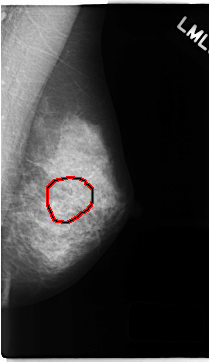

C_0142_1.RIGHT_MLO

LEFT_MLO LINES 4696 PIXELS_PER_LINE 2712 BITS_PER_PIXEL 12 RESOLUTION 50 OVERLAY

FILE: C_0142_1.LEFT_MLO.OVERLAY

TOTAL_ABNORMALITIES 1

ABNORMALITY 1

LESION_TYPE MASS SHAPE ARCHITECTURAL_DISTORTION MARGINS ILL_DEFINED

ASSESSMENT 3

SUBTLETY 3

PATHOLOGY MALIGNANT

TOTAL_OUTLINES 1

BOUNDARY